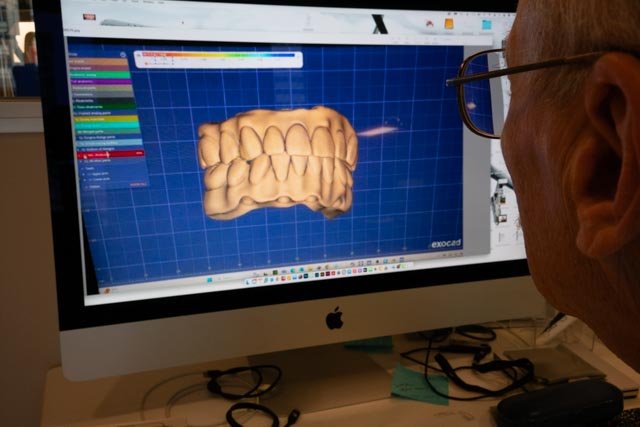

- What is the process for getting All-on-4 implants?

The procedure includes consultation, imaging, implant placement, and fitting of a temporary prosthetic. After healing (4–6 months), a permanent prosthetic is placed.